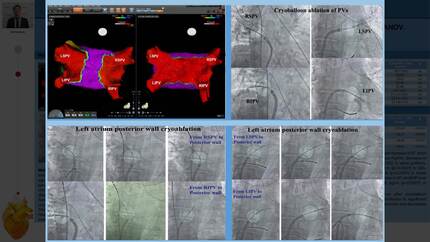

Atrial fibrillation cryoablation in heart failure patients with systolic dysfunction: long-term period outcomes

Impact of altered pulmonary vein anatomy on long-term outcomes after cryoablation of paroxysmal atrial fibrillation